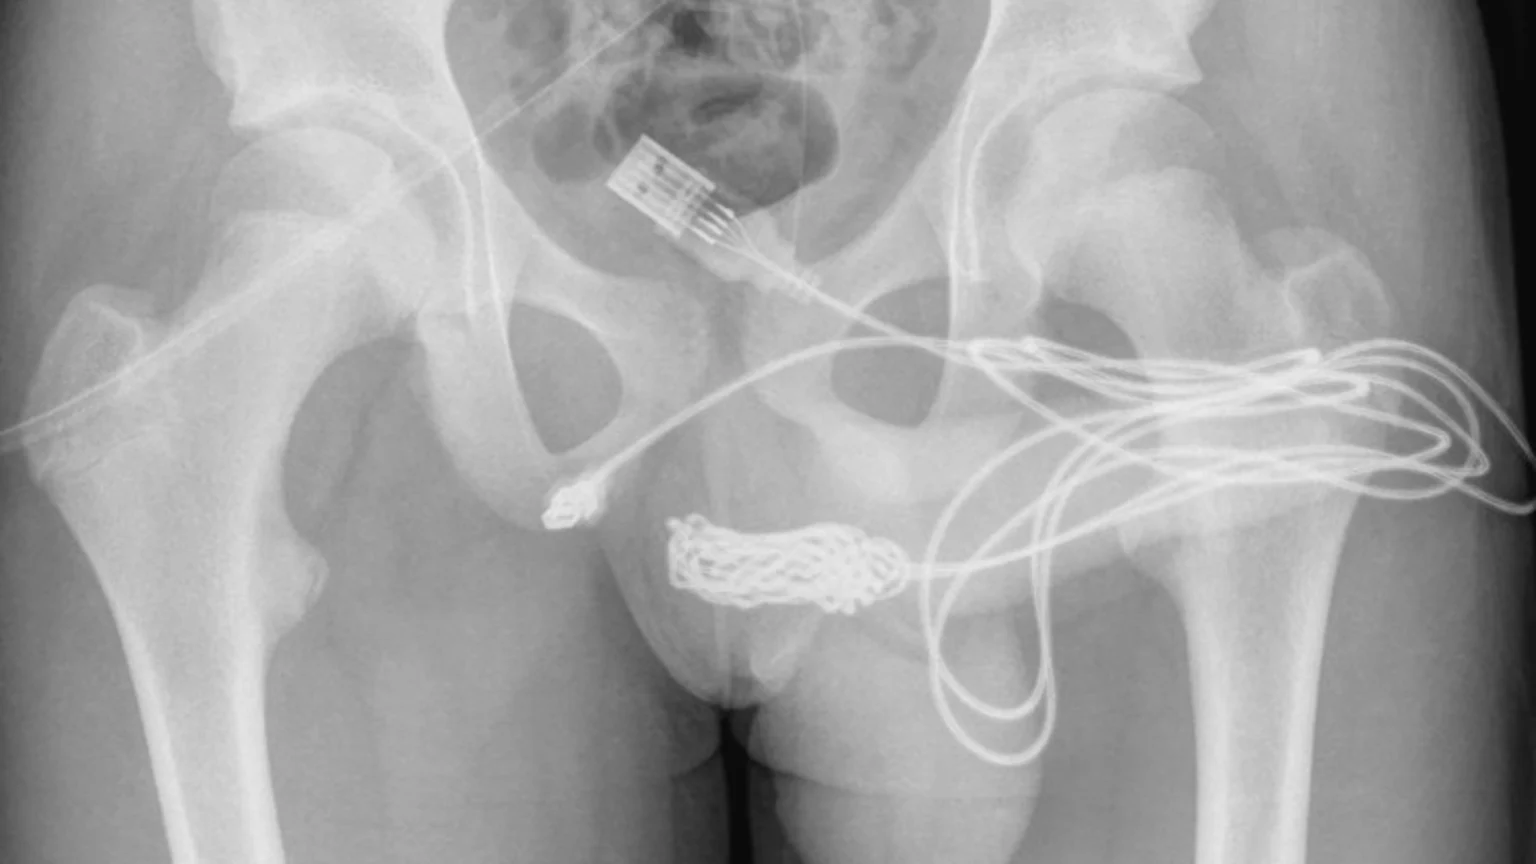

Initial attempts to remove it failed. After getting it X-rayed the surgeons decided the best way to get it out was to open up his gooch, between his penis and butthole to yank it out. Literally pulling the plug on the boy's nasty ordeal.